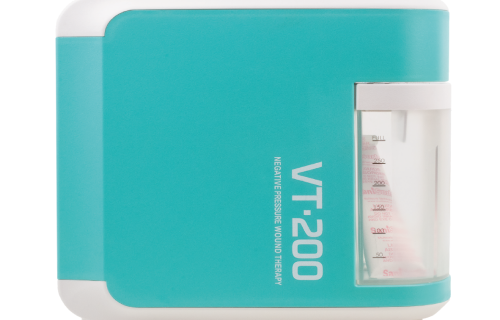

Além disso, fornecemos soluções para o tratamento de feridas que promovem a cicatrização eficiente e segura para os pacientes. Nossos dispositivos de Terapia por Pressão Negativa são projetados para criar um ambiente ideal de cura, reduzindo o risco de infecções e acelerando o processo de cicatrização. Essas soluções são amplamente utilizadas em feridas crônicas,

úlceras de pressão, feridas pós-cirúrgicas e traumas, oferecendo uma alternativa eficaz e inovadora para o manejo de feridas complexas.